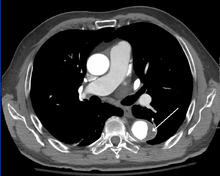

Computed tomography

Computed tomography angiography is a fast, noninvasive test that gives an accurate three-dimensional view of the aorta. These images are produced by taking rapid, thin-cut slices of the chest and abdomen, and combining them in the computer to create cross-sectional slices. To delineate the aorta to the accuracy necessary to make the proper diagnosis, an iodinated contrast material is injected into a peripheral vein. Contrast is injected and the scan performed using a bolus tracking method. This type of scan is timed to an injection to capture the contrast as it enters the aorta. The scan then follows the contrast as it flows though the vessel. It has a sensitivity of 96 to 100% and a specificity of 96 to 100%. Disadvantages include the need for iodinated contrast material and the inability to diagnose the site of the intimal tear.